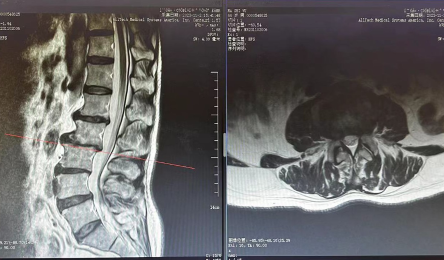

• 腰椎間盤突出别擔心,針刀治療顯奇效

2024-03-01

“大(dà)夫,我的腿痛得(de)很,走不了路(lù),隻能坐(zuò)輪椅,太痛苦了。我不想手術(shù),可(kě)以保守治療嗎(ma)?” 這是患者馬師(shī)傅來(lái)到我院康複醫學科(kē),跟王康醫生(shēng)說(shuō)的第一句話(huà)。 患者情況 馬師(shī)傅以間斷性腰背部疼痛3月...